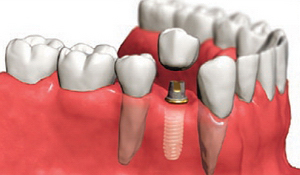

İmplant (Diş kökü olmayan bölgelere uygulanan suni kökler)